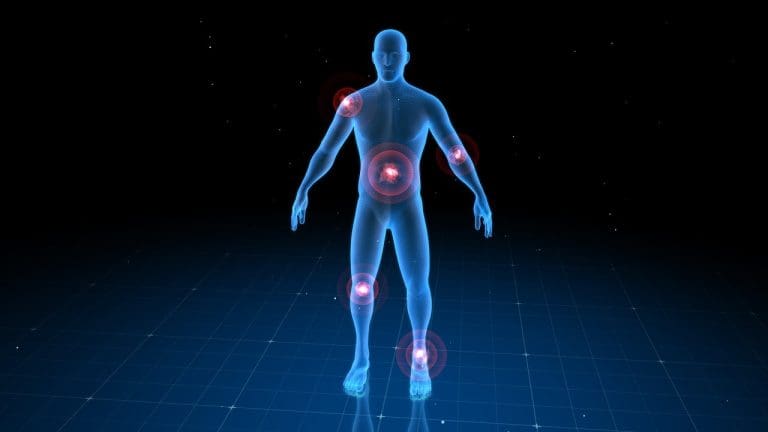

Does a Bone Scan Show Arthritis?

It’s important to know how arthritis shows up on bone scans for the right diagnosis and treatment. Bone scans are a key tool for spotting bone issues, including arthritis.

How Arthritis Appears on Bone Scans

Arthritis shows up on bone scans as spots where the tracer uptake is higher. This usually means there’s inflammation or damage in the joints. The amount of uptake depends on how severe and what type of arthritis it is.

In osteoarthritis, the scan might show more uptake in the affected joints. This is because of bone changes and inflammation. Rheumatoid arthritis also shows up with more uptake, due to inflammation and damage in the joints.

Types of Arthritis Visible on Scintigraphy

Bone scintigraphy can spot different types of arthritis, including:

- Osteoarthritis

- Rheumatoid arthritis

- Psoriatic arthritis

- Ankylosing spondylitis

Each type of arthritis has its own pattern on the bone scan. This helps doctors diagnose and understand how severe the disease is.

Typical Patterns of Arthritic Changes

The patterns seen on bone scans can help doctors diagnose arthritis. For example, osteoarthritis usually affects joints unevenly. On the other hand, rheumatoid arthritis tends to affect joints more evenly.

Bone Scan Arthritis vs Cancer: Distinguishing Patterns

Understanding bone scans to tell apart arthritis and cancer is tricky. It needs a deep grasp of the patterns each condition shows.

Distribution Differences

The way tracer uptake spreads on a bone scan can hint at the cause. Arthritis usually shows up in a specific, symmetrical way, hitting both sides of the body’s joints. Cancer, on the other hand, spreads randomly and unevenly, hitting many parts of the skeleton.

For example, arthritis might show up in joints like the hips and knees, and the spine. But cancer can pop up in places like ribs, pelvis, and vertebrae, without a clear pattern.